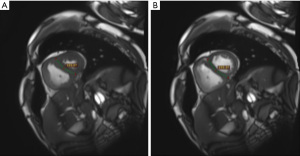

The LV eccentricity index (LVEI) reflects the degree of LV deformation and is defined as the ratio of the anteroposterior diameter to the septal-free wall diameter of the LV (34,35,65) (Figure 2A,2B). Systolic LVEI showed a good ability to diagnose pre-PH, with an AUC of 0.87 for systolic LVEI >1.2 (sensitivity 70%, specificity 94%) (33). At a discrimination threshold yielding 73% sensitivity and 93% specificity, systolic LVEI showed high diagnostic accuracy (AUC =0.90, overall accuracy 89%) for identifying PH in untreated congenital heart disease (CHD) patients (34). Interestingly, systolic LVEI was higher in patients with CHD combined with RV myocardial fibrosis (34), which implies that this parameter may predict RV myocardial fibrosis. In addition to its diagnostic and classificatory value, LVEI also has prognostic value in PH. A study that included 38 pediatric PH patients demonstrated that both systolic and diastolic LVEI predicted graft-free survival in children with IPAH/hereditary PH (35), indicating its potential for risk stratification in pediatric PAH.